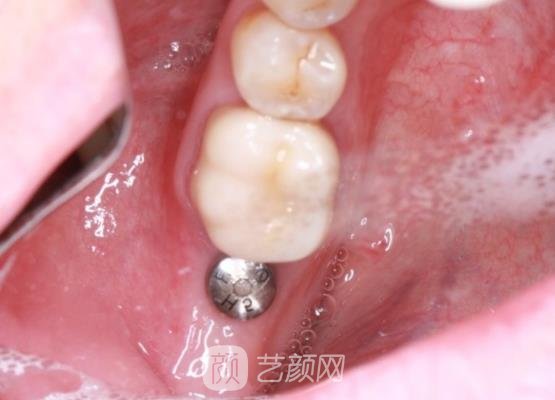

确定手术方案后,手术就开始了,刚开始我还是比较紧张的,不过幸亏有医生一直在旁边不断的安慰我,我紧张的情绪才缓解了很多,短短几个小时手术也就结束了,并没有浪费我很多的时间。

刚结束手术时,我的牙龈有一些肿胀的情况,还很疼,医生告诉这些现象比较正常,让我不用太过于担心,然后检查一下我的牙龈情况,帮我开了几副消炎药,让我定时服用。

几个月后,我的种植牙已经恢复好了,看起来真的很自然,就像我自己的牙齿一样,现在我终于可以大吃特吃了,前几天和朋友们出去吃饭的时候,朋友们也都说我的手术进行的很顺利。